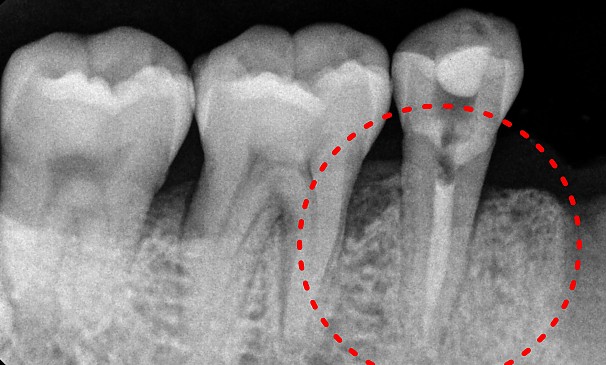

한OO님 전후사진 | 치료 기간 : 2주

치료 전

치료 후

특수신경치료